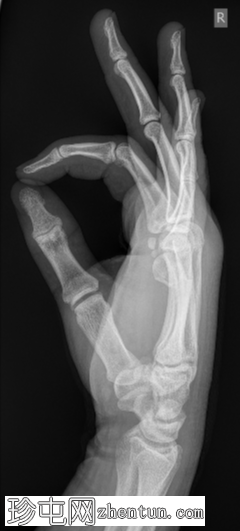

X线片

正位片

斜位片

侧位片

右手第五掌骨颈骨折,即“拳击手骨折”。轻度粉碎性骨折,部分嵌插,骨端背侧成角。

掌骨骨折是最常见的手部损伤类型,其中第五掌骨颈骨折(即拳击手骨折)占所有手部骨折的10%。其机制通常是握拳撞击坚硬平坦的表面。

本病例需要手术治疗,采用切开复位内固定术,使用钢板和螺钉固定。